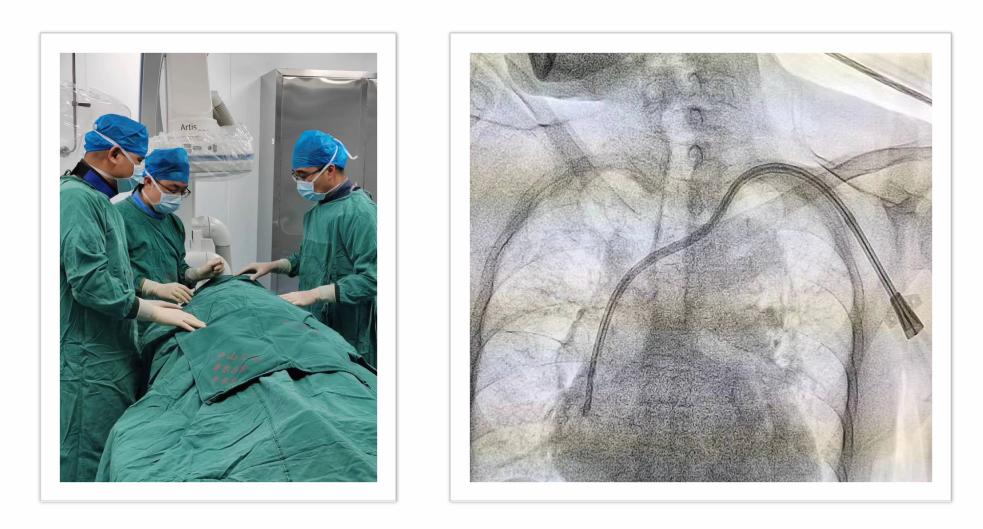

常规开展超声介入及DSA(数字减影血管造影)引导下的动静脉内瘘球囊扩张术、中心静脉狭窄扩张术、外周血管支架置入术及疑难长期导管置换,实现血管通路的“建立-维护-并发症处理”全周期诊疗管理。

动静脉内瘘球囊扩张术(PTA术)

DSA下血管通路介入治疗